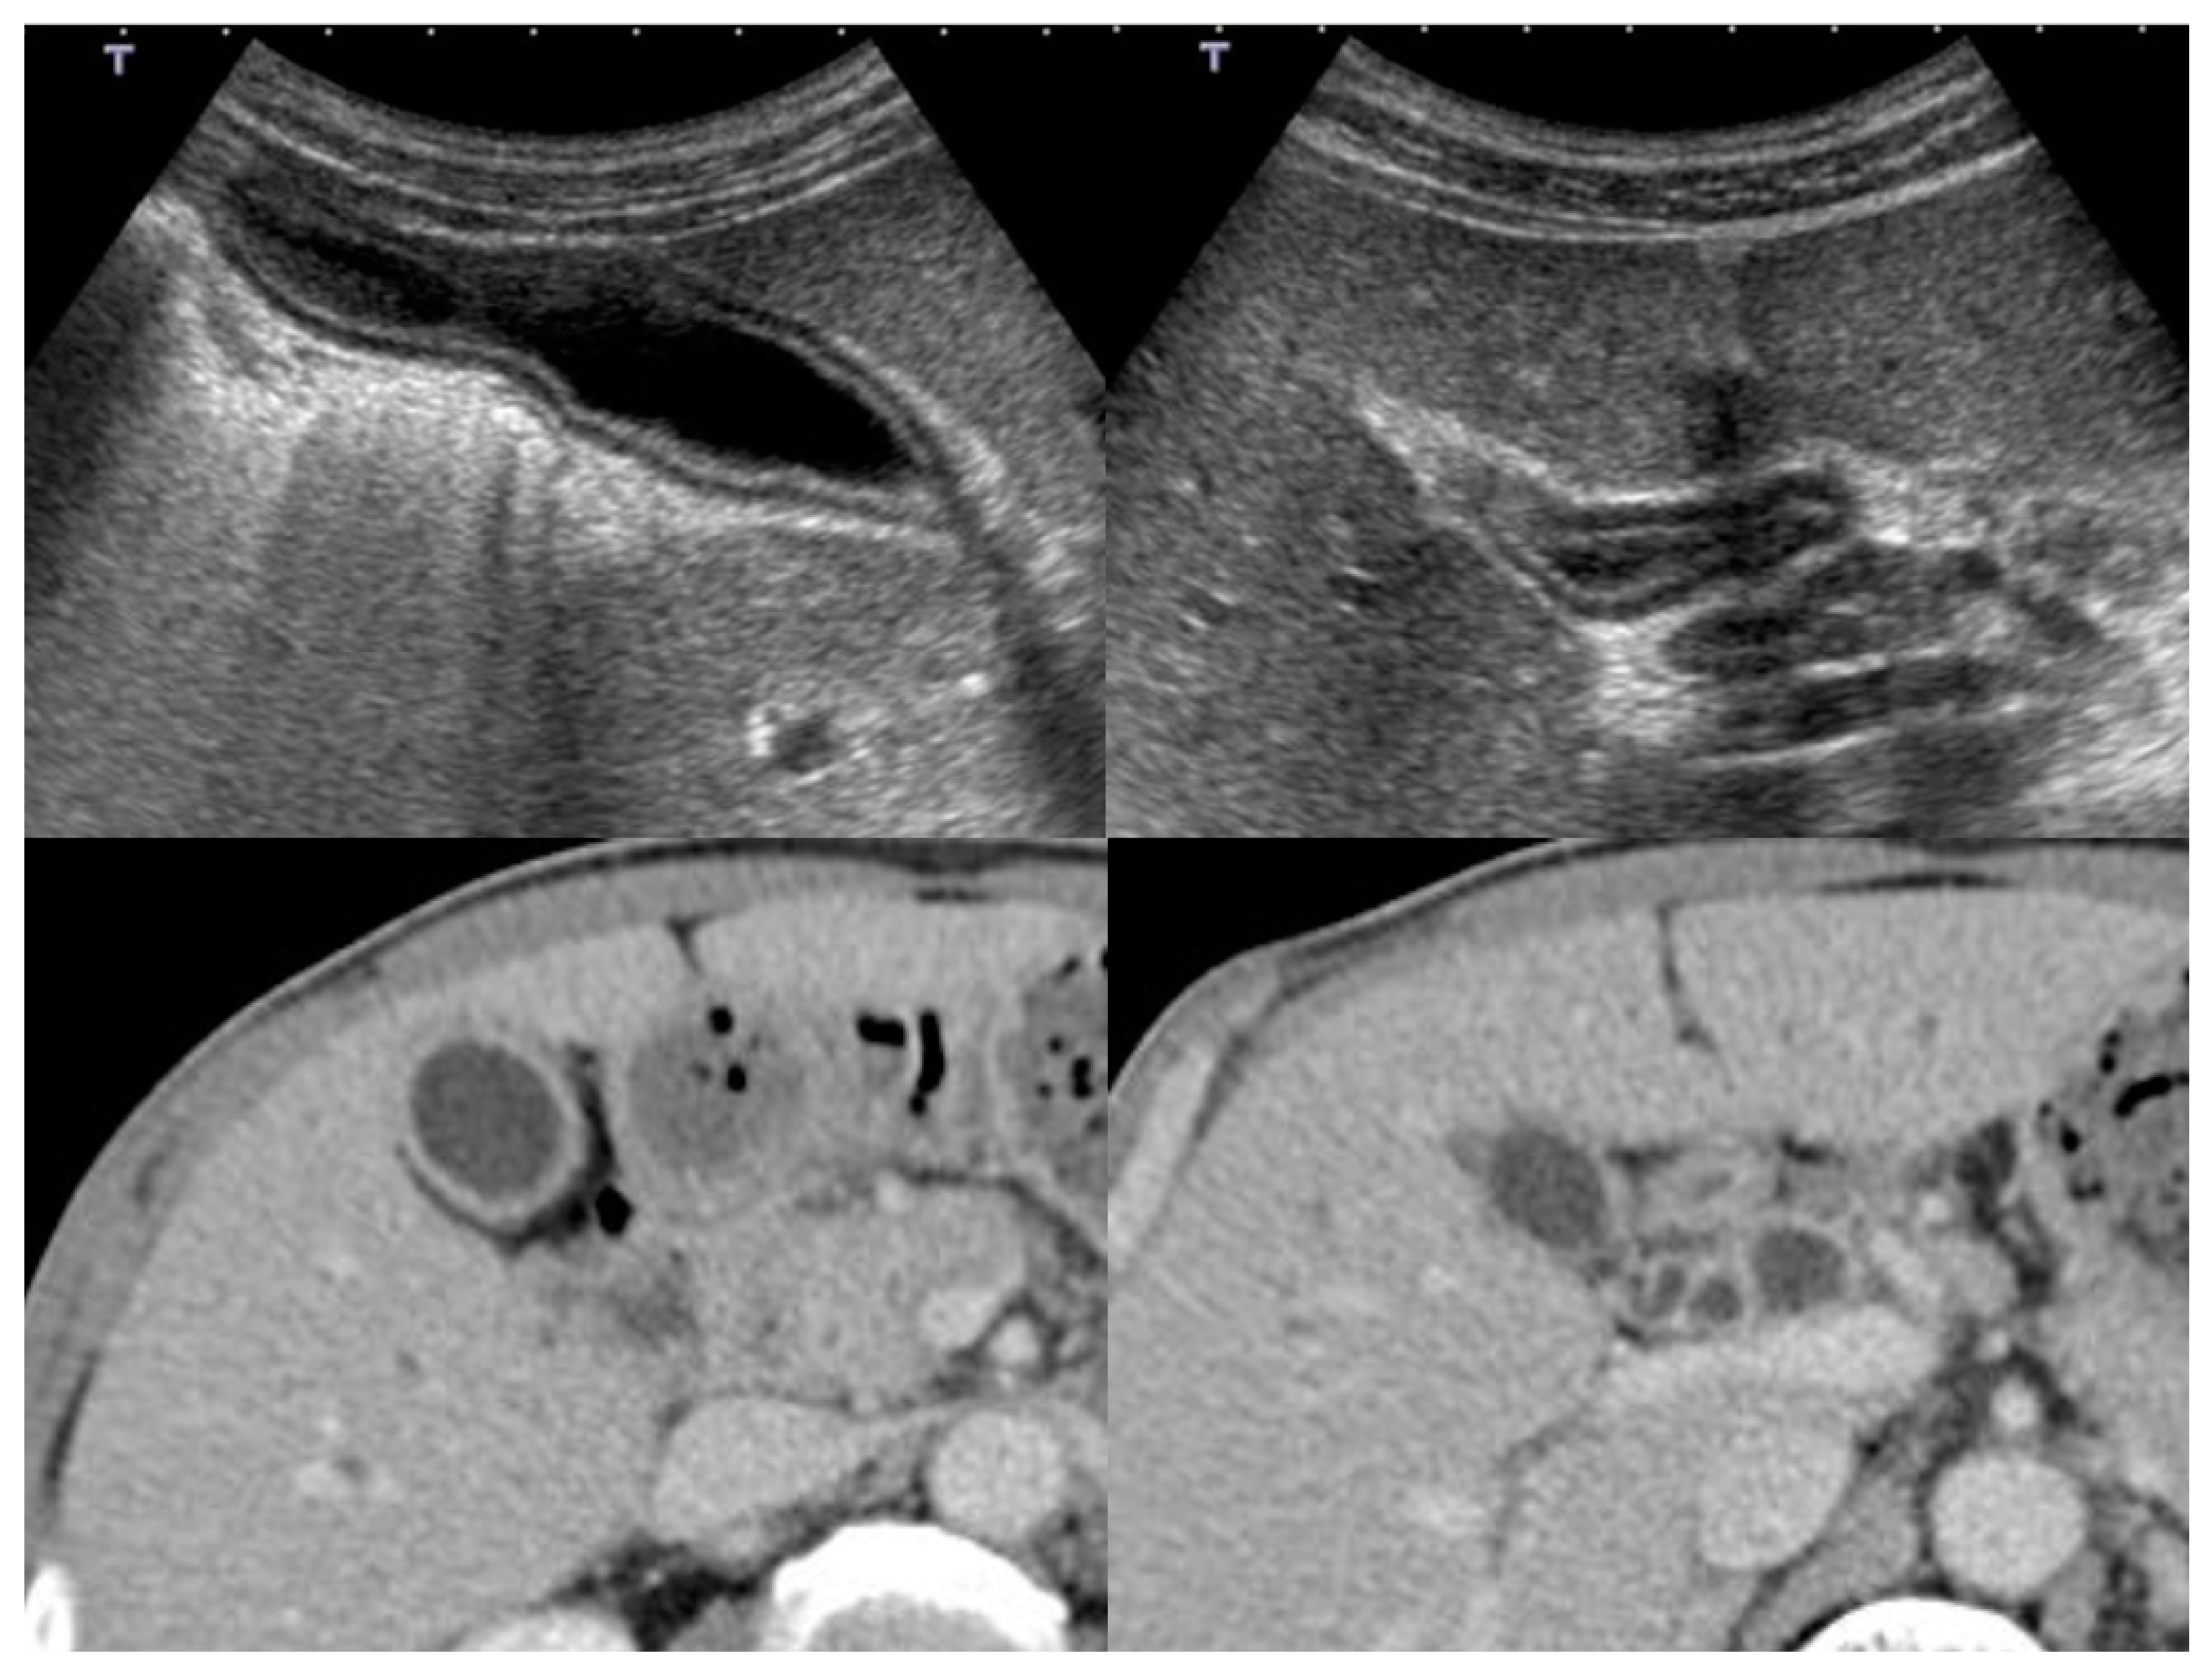

4.1. Diffuse Type of IgG4-CC

4.2. Localized Type of IgG4-CC